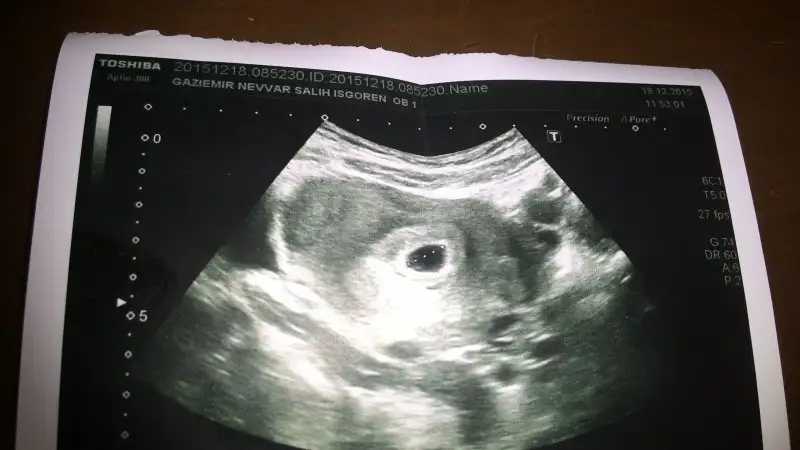

Yok canım ikiz değil alttaki yumurta kistiymis kendiliğinden gecer dedi Dr ama korkuyorum yinede. Birde 27 haftalık bir kaybim varİkiz mi cnm,üst kesede olanda bebek görülüyor alttakinde göremedim.üstteki için yorum yapacağım.usg karındansa erkek gibi vajinalsa kız gibi